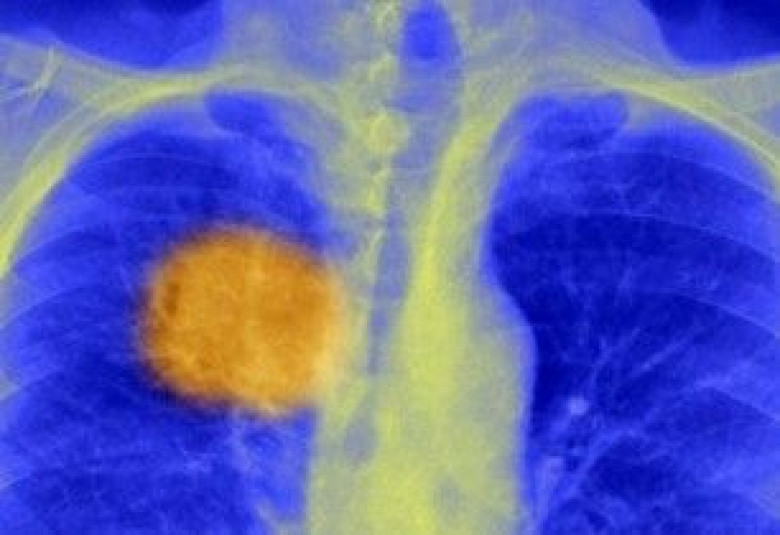

Բրիտանացի գիտնականները խոստանում են՝ շուտով քաղցկեղը հաղթահարել մեկ սրսկումով

BBC-ն տեղեկացնում է, որ բրիտանացի գիտնականները խոստանում են առաջիկայում մարդու դիմադրողական համակարգին ստիպել ավելի արդյունավետ պայքարել քաղցկեղի ուռուցքների դեմ:

Լոնդոնի համալսարանական քոլեջի գիտնականները հայտնում են, որ այժմ գտել են քաղցկեղի կառուցվածքում «թույլ» հատվածների հայտնաբերման համապատասխան մեխանիզմը:

Դա ենթադրում է անհատական մոտեցում դեպքերից յուրաքանչյուրի պարագայում: Տեսկանորեն դա կարող է շատ թանկ արժենալ, բայց արդեն ոչ թե քիմիաթերապիայի տեսքով, այլ ընդամենը մեկ սրսկոցով իրականացվող բուժման՝ հիվանդի ուռուցքից դուրս բերված պրոտեինների հիման վրա պատրաստված պատվաստանյութով: Այդ պատվաստանյութը դիմադրողական համակարգը կգործարկի՝ չարորակ ուռուցքի դեմ պայքարում:

Գիտնականները հայտնել են, որ սա վերջին տարիներին գրանցված ամենախոշոր առաջընթացն է այս ոլորտում և կարող է լրիվ փոփոխել քիմիաթերապիան և ճառագայթաբուժությունը: